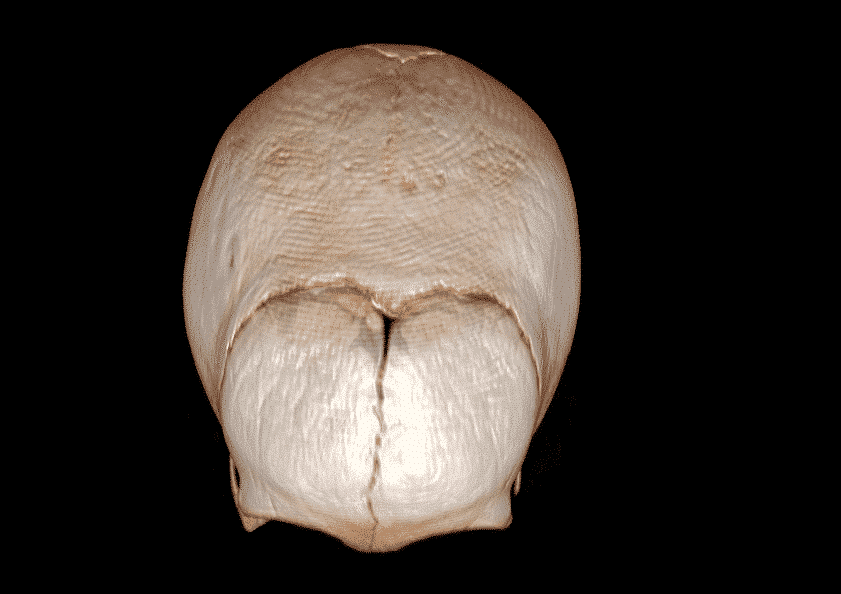

Results: A 3-month-old female infant consulted in primary care due to cranial deformity. Physical examination shows good general condition, well nourished and highlights cranial deformity with the appearance of scaphocephaly. Her head circumference was above 80 percentile for her age. There were no apparent facial deformities and age appropriate developmental milestones were achieved. Her birth history included an uneventful spontaneous vaginal delivery at 39 weeks, her natal weight was 3.4kg and there was an hospital admission at one month of life due to fever and marginal erythema with normal infectious study. The patient underwent thin slice high resolution cranial CT examination using multi-slice CT scanning and reconstruction images were obtained for 3 dimensional analysis. The scan revealed premature fusion of sagittal suture.The patient is now 8-month-old and is undergoing neurosurgery follow-up due to good neurological development and adequate cranial growth.